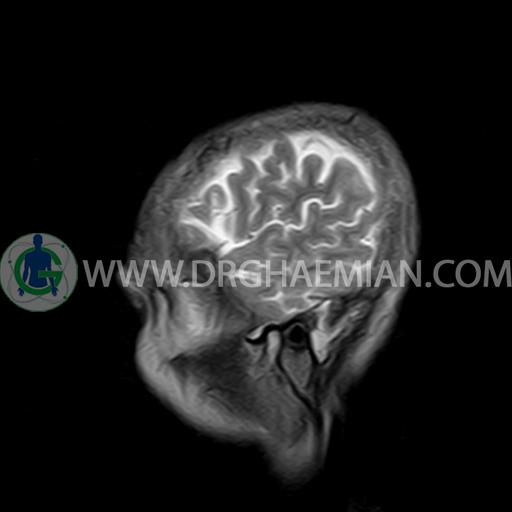

ام آر آی مغز با استفاده آهنربا های قوی و امواج رادیویی تصاویری از مغز و بافت های عصبی پیرامونی آن ایجاد می کند. در این کیس مننژیوم به همراه هیپراستوز استخوانی سمت چپ دیده می شود.

a well – defined dural based mass lesion ( 27x55mm ) in left parietal region with signal change in adajacent bone suggestive for meningioma with bone hyperosteosis

mass effect & edema in left parietal lobe

are seen